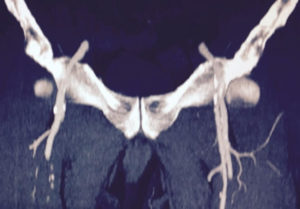

La enfermedad arterial periférica es la principal causa de amputaciones en extremidades inferiores, los factores de riesgo son tabaquismo (fumadores activos o pasivos) y diabetes mellitus. Es